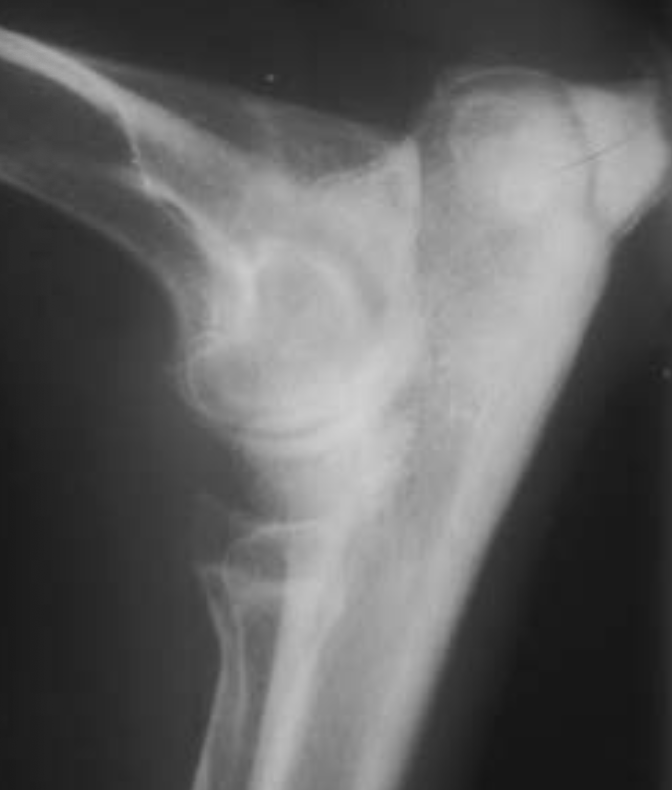

3.5m Yorkie

lateral humeral condylar fracture - see its caudal displacement, superimposed over the cranial ulna.